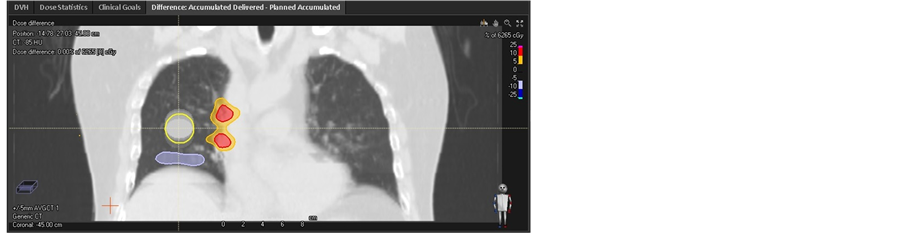

However, in presence of proton range uncertainty of +/−3.5% [20] [21] , the dispersion of DVHs significantly increase based both CTavg_tumor and CTavg_muscle. DVH for GTV on each phase was displayed on Figure 6. In the worst case, GTV D98 decrease to 51.96 Gy in phase −5 mm on CTavg_tumor based plan, while D98 of GTV decrease to 55.96 Gy in phase −5 mm on CTavg_muscle based plan. Detail result was listed in Table 2. Figure 7 shows the GTV coverage difference between the accumulative dose and planned dose.

Figure 6. DVHs of different phase for GTV with initial pan based (a) CTavg_tumor considering 3.5% proton range overestimate, (b) CTavg_tumor considering 3.5% proton range underestimate, (c) CTavg_muscle considering 3.5% proton range overestimate, (d) CTavg_ muscle considering 3.5% proton range underestimate.

Figure 7. Comparison of DVHs for GTV between accumulation and initial plan based (a) CTavg_tumor, (b) CTavg_muscle.